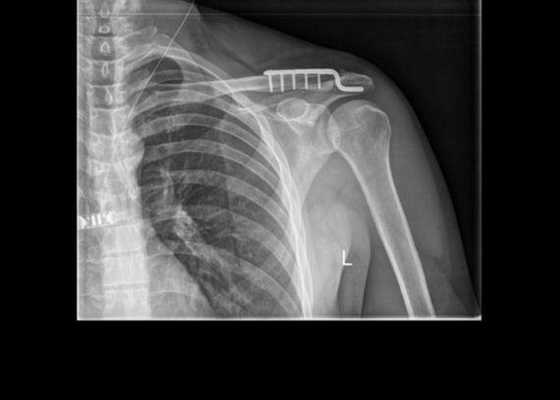

Вправление вывиха ключицы

Методы вправления консервативные или хирургические. Это зависит от степени тяжести клинического случая, количества времени, прошедшего после травмирования, и разновидности вывиха ключицы (со всеми видами можно детально ознакомиться здесь). Вправление осуществляется открытым или закрытым способом. При повреждении ключицы чаще прибегают к хирургической манипуляции. Только при условии, что травма свежая и не сопровождается осложнениями, возможно проведение закрытой репозиции с дальнейшей фиксацией конечности на несколько недель.

Передний вывих грудинного конца

Врач тянет пациента за поврежденную руку, одновременно нажимая на выпирающий конец ключицы. Репозиция проходит быстро, но после того как пациент встанет с кушетки, есть риск того, что конец S-образной кости вновь покинет свое анатомическое положение. Если это произошло, прибегают к операции. Вероятность положительного исхода от закрытой репозиции - 50%.

Полный задний вывих

В легком случае, когда мягкие ткани не повреждены вследствие зажатия между суставными частями, вправление не вызывает сложностей. Суть процедуры: врач поднимает плечо, отводит его назад, одновременно с этим надавливает пальцами на наружный конец S-образной кости.

Поскольку удержать ключицу во вправленном положении сложно, поэтому травматолог ее фиксирует гипсовой повязкой, в подмышечную впадину кладет ватный валик. Перед наложением фиксирующей повязки вводит Новокаин для обезболивания.

Длительность фиксации - не менее 1 месяца. Со второго дня начинается реабилитационная программа. Первый ее этап - движения пальцами для приведения мышц верхней конечности в тонус с целью предупреждения атрофии.

Вывих грудинного конца

Это довольно редкий вид повреждения, который возникает вследствие непрямой травмы конечности. Вправление осуществляется под местным наркозом. В сустав вводится 10 мл Новокаина. Для проведения закрытой репозиции нужны 2 человека. Помощник оттягивает за спину к серединной линии одновременно 2 сустава плеча, в это время врач надавливает на вывихнутый конец. Процедура несложная, в отличие от задачи удержать кость в нужном положении. После репозиции накладывается восьмиобразная повязка.

Лоскутный с основанием к грудине разрез обнажает грудино-ключичное сочленение и внутреннюю ключичную кость. Удаляются скопившиеся сгустки крови и части поврежденных мягких тканей. Диск с ключицей вправляются.

Фиксация восстановленной ключичной кости осуществляется несколькими способами:

- в конце ключицы и суставной грудинной вырезке просверливается по несколько отверстий, через них проводится шелковая нить или узкая полоса широкой фасции бедра;

- просверливание в ключице канала, через который пропускается лавсановая лента или полоса свободной фасции, один из концов обводится вокруг первого ребра, концы натягивают и сшивают;

- проведение спиц через ключицу, грудину и грудино-ключичный сустав.

Метод со спицами сложный, поскольку орудовать данными приспособлениями нужно осторожно, не допуская их проникновения в переднее средостение. Концы спиц загибают, чтобы предупредить их миграцию. После операции рекомендуется зафиксировать ключицу путем наложения на руку шины отводящего типа.